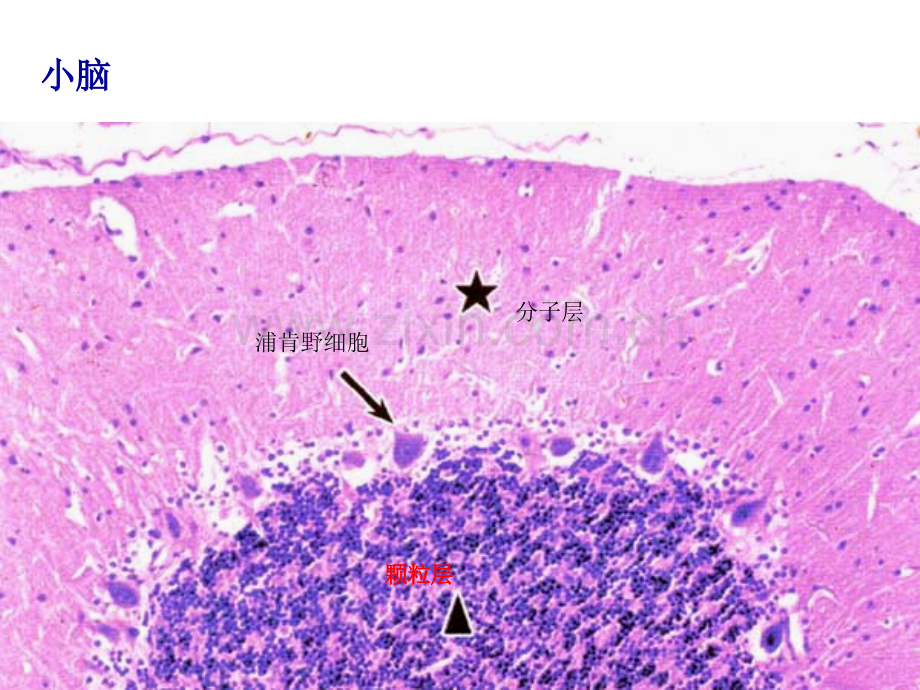

颗粒层颗粒层浦肯野细胞分子层小脑小脑十二指肠腺绒毛绒毛小肠皱襞小肠皱襞十二指肠腺小肠腺黏膜肌胃底腺腔主细胞小肠皱襞黏膜下层肌层平滑肌中央乳糜管壁内皮细胞小小肠肠哪哪一一段段回肠潘氏细胞箭头所示:箭头所示:浆半月浆半月45.箭头所指为?胸腺小体粘膜下层粘膜下层粘膜下层粘膜下层?黏膜(上皮、固有层、黏膜肌)肌层(内肌层(内肌层(内肌层(内环外纵)环外纵)环外纵)环外纵)粘膜下层粘膜下层粘膜下层粘膜下层 外膜外膜外膜外膜 食管食管食管食管辨认该图是哪段消化管?辨认该图是哪段消化管?食管食管血管球近端小管远端小管辨认该图为消化管哪个部位?辨认该图为消化管哪个部位?食管上皮与胃贲门粘膜交界处下颌下腺下颌下腺闰管闰管壁细胞主细胞中动脉中静脉 胰胰 腺腺 外外 分分 泌泌 部部泡心细胞泡心细胞闰管闰管何种器官?箭头所指为?淋巴结淋巴结淋巴小结何种器官?脾脾箭头所指为?红髓红髓绿色圆所圈的结构为?白髓白髓此器官的名称此器官的名称高倍高倍低倍低倍肝肝胰岛胰岛闰管肺泡管(肝细胞索;肝细胞索;肝血窦)肝血窦)小叶间胆管小叶间动脉门管区门管区小叶间静脉小叶间静脉肾小体肾小体肾小体肾小体肾小体箭头所示的箭头所示的结构结构名称名称.细支气管肝巨噬细胞肝巨噬细胞黑色箭头所指为?黑色箭头所指为?胰岛 此器官为?此器官为?胰腺 写出此器官的名称:写出此器官的名称:淋巴结淋巴结 此器官的名称此器官的名称 胸腺胸腺肝小叶局部(高倍)胆小管胆小管内膜内膜?内弹性膜内弹性膜 外膜中膜外弹性膜 小动脉小动脉 小静脉小静脉 肝小叶中央静脉 气管粘膜(左)和混合性腺(右)气管粘膜(左)和混合性腺(右)肺内小支气管肺内小支气管细支气管细支气管辨认该图为哪段器官分支?肺内小支气管肺内小支气管小支气管小支气管细支气管细支气管细支气管细支气管 终末细支气管、呼吸性细支气管、肺泡管终末细支气管、呼吸性细支气管、肺泡管 小支气管小支气管二型肺泡细胞一型肺泡细胞肺泡隔1 型肺泡细胞,型肺泡细胞,2 型肺泡细胞,型肺泡细胞,肺巨噬细胞II 型肺泡细胞型肺泡细胞嗜锇性板层小体嗜锇性板层小体肾髓质肾髓质肾皮质肾皮质皮质迷路髓放线皮质迷路出、入球微动脉出、入球微动脉箭头所示:球外系膜细胞箭头所示:球外系膜细胞肾小囊肾小囊肾小囊肾小囊远端小管近端小管CD为集合小管;箭头所示细段为集合小管;箭头所示细段球旁细胞球旁细胞 血管球血管球 近端小管刷状缘近端小管刷状缘近端小管刷状缘近端小管刷状缘近端小管刷状缘近端小管刷状缘致密斑致密斑致密斑致密斑膀胱膀胱黏膜肌层外膜帽明区暗区胸腺胸腺光镜像(光镜像(被膜被膜 皮质皮质 髓质)髓质)胸腺小体淋巴结淋巴结 肾浅层皮质肾浅层皮质 :小结间区:小结间区副皮质区副皮质区 T淋巴淋巴细胞、毛细血管后微静脉细胞、毛细血管后微静脉被膜被膜皮质淋巴窦皮质淋巴窦淋巴结髓质淋巴结髓质小梁小梁髓索髓索髓窦髓窦脾小梁淋巴小结淋巴小结中央动脉中央动脉红髓红髓动脉周围淋巴鞘动脉周围淋巴鞘脾小体脾小体箭头所示:动脉周围淋巴鞘隐窝箭头所示:心脏束细胞箭头所示:心脏束细胞箭头所示:心外膜(浆膜)箭头所示:心外膜(浆膜)箭头所示:箭头所示:心心瓣膜瓣膜中动脉内弹性膜内弹性膜外弹性膜外弹性膜 小动脉(小动脉()和小静脉(和小静脉()光镜图光镜图微动脉纵切面微动脉纵切面 箭头所示:箭头所示:静脉瓣静脉瓣球状带束状带网状带辨认该图为哪种激素细胞?含氮类含氮类辨认该图为哪种激素细胞?类固醇类类固醇类箭头所示:箭头所示:甲状腺滤泡旁细胞甲状腺滤泡旁细胞垂体远侧部垂体远侧部 特殊染色特殊染色嗜嗜碱碱性细胞性细胞嗜嗜酸酸性细胞性细胞嫌色细胞嫌色细胞结缔组织结缔组织垂体远侧部垂体远侧部垂体细胞;垂体细胞;赫令体赫令体分子层分子层分子层分子层 外颗粒层外颗粒层外颗粒层外颗粒层 外锥体层外锥体层外锥体层外锥体层 内颗粒层内颗粒层内颗粒层内颗粒层 内锥体层内锥体层内锥体层内锥体层 多形细胞层多形细胞层多形细胞层多形细胞层 1 2 3 4 5 61 2 3 4 5 6大脑皮质分层大脑皮质分层大脑皮质分层大脑皮质分层 大脑皮质锥体细胞大脑皮质锥体细胞大脑皮质锥体细胞大脑皮质锥体细胞(分子层分子层分子层分子层 蒲肯野细胞层蒲肯野细胞层蒲肯野细胞层蒲肯野细胞层 颗粒层颗粒层颗粒层颗粒层 白质白质白质白质)箭头所示:箭头所示:蒲肯野细胞蒲肯野细胞蒲肯野细胞蒲肯野细胞 脊髓前角脊髓前角脊髓前角脊髓前角(运动神经元运动神经元运动神经元运动神经元 运动神经元运动神经元运动神经元运动神经元)脊神经节细胞;脊神经节细胞;脊神经节细胞;脊神经节细胞;卫星细胞(神经胶质细胞)卫星细胞(神经胶质细胞)卫星细胞(神经胶质细胞)卫星细胞(神经胶质细胞)脉络丛脉络丛脉络丛脉络丛 (上皮上皮上皮上皮 血管血管血管血管)此课件下载可自行编辑修改,供参考!此课件下载可自行编辑修改,供参考!部分内容来源于网络,如有侵权请与我联系删除!部分内容来源于网络,如有侵权请与我联系删除!